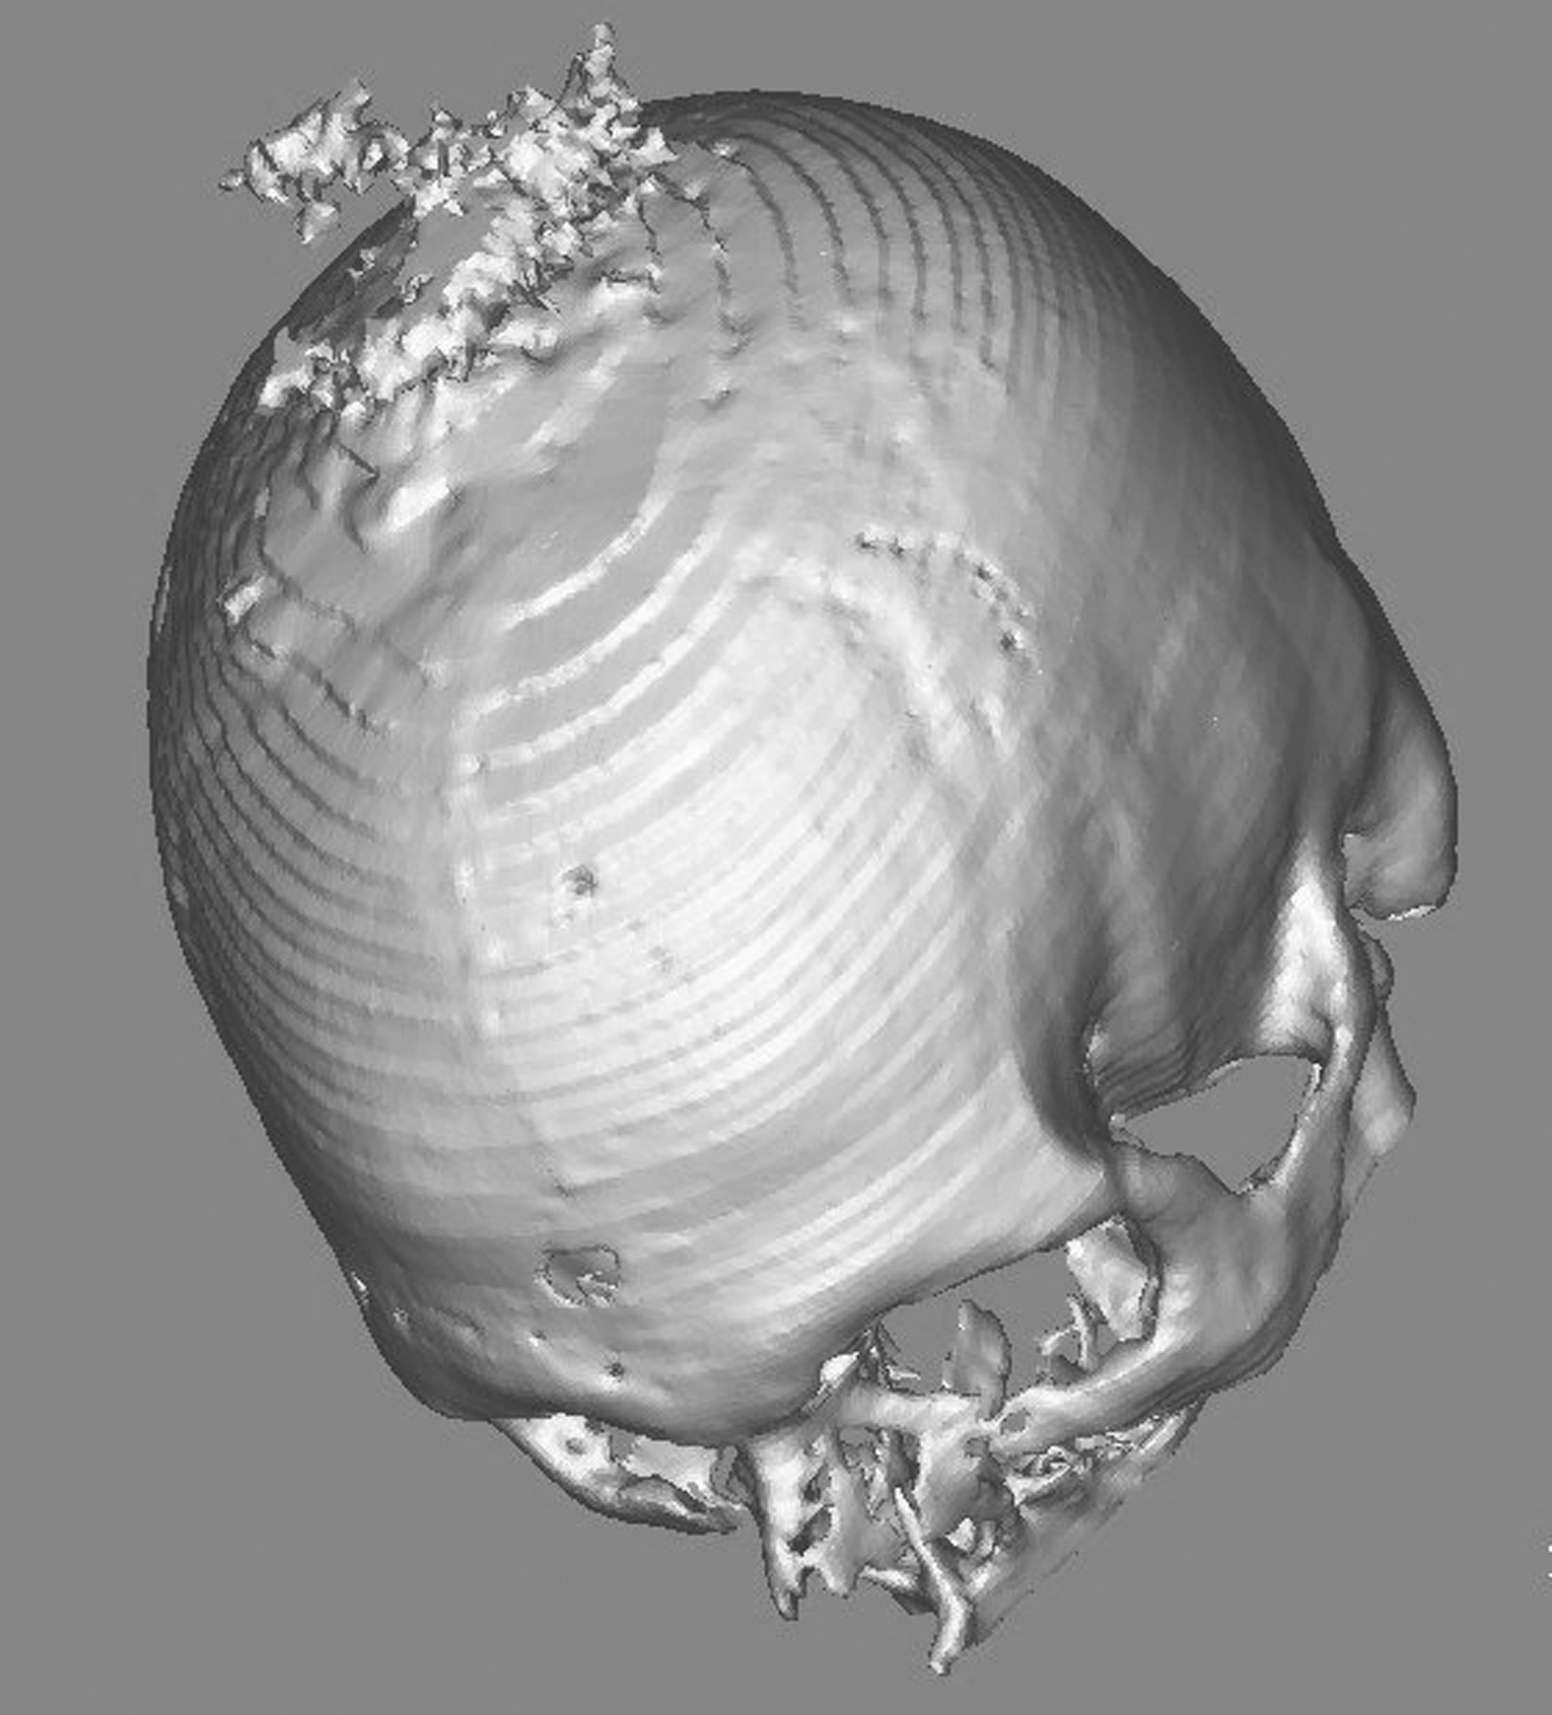

Figura

2. Implementazione delle immagini con quelle RM al

neuronavigatore. Caso di un voluminoso meningioma della volta, intra

ed extracranico, con coinvolgimento tecale. Sotto, a sinistra,

studio preliminare con ricostruzione 3D al computer; a destra,

modello 3D in resina dove si rileva il contorno della superficie da

asportare. |